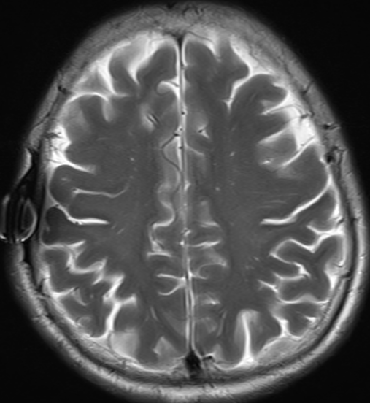

2015-4-1 MRI

2015-4-1